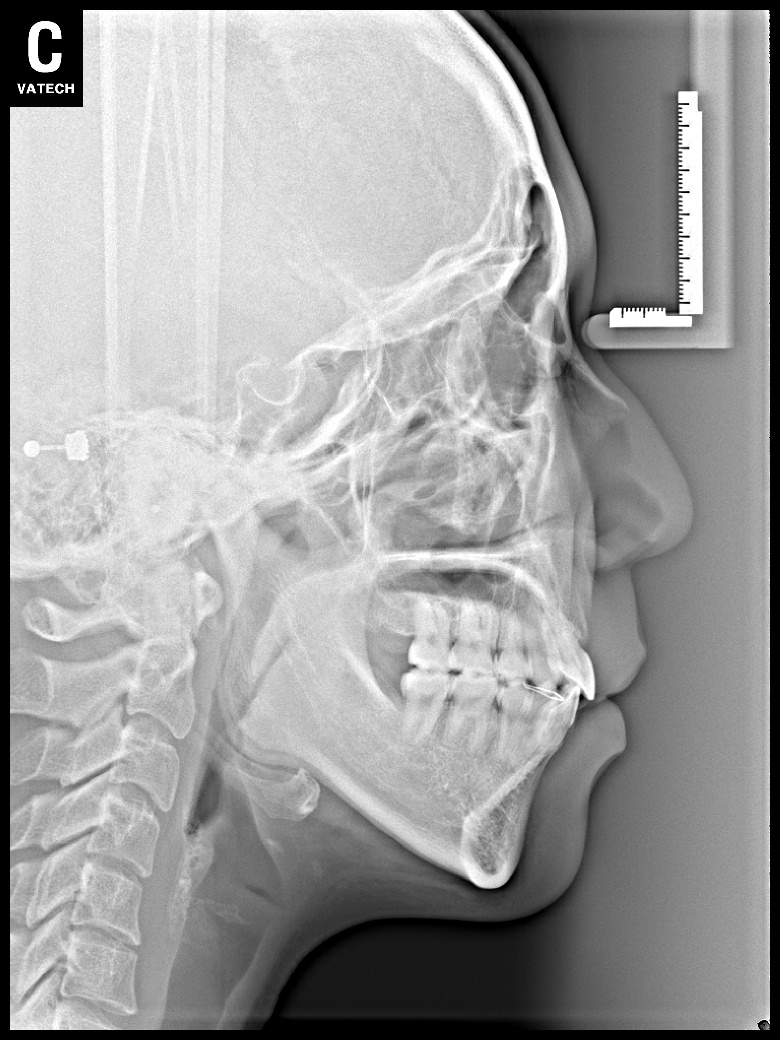

치료 후 사진입니다.